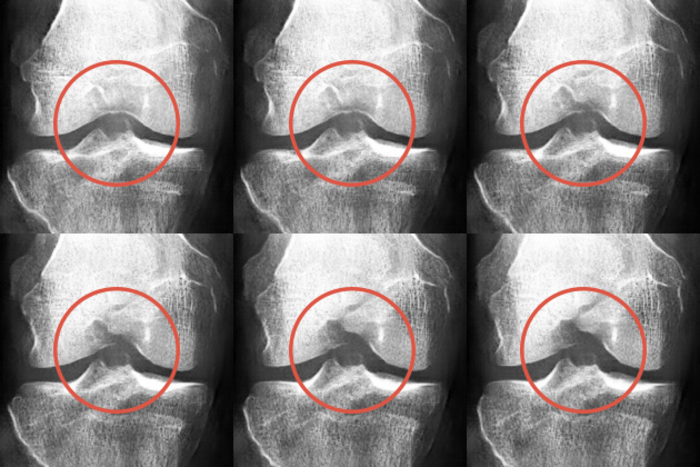

Adjacent image show a set of screenshots of an animation showing how a synthetic x-ray can be modified to expert specifications.

A group of researchers from University of Jyväskylä's AI Hub Central Finland project developed an AI based method to create synthetic knee x-ray images to replace or complement real x-ray images in knee osteoarthritis classification.

Researchers used synthetically generated X-ray images to complement a data set of real X-ray images from the osteoarthritis study. The authenticity of the images was then assessed together with specialists from the central Finland healthcare district.

Medical experts were asked to rate osteoarthritis severity without knowing that the data set included synthetic images. In the second phase, experts tried to identify authentic and synthetic images. The results showed that on average, it was improbable even for medical experts to distinguish between real and synthetic x-ray images.

“By mixing real and synthetic x-ray images, we improved AI-based osteoarthritis classification systems”, says Fabi Prezja , the Doctoral Researcher responsible for developing the artificial neural network.